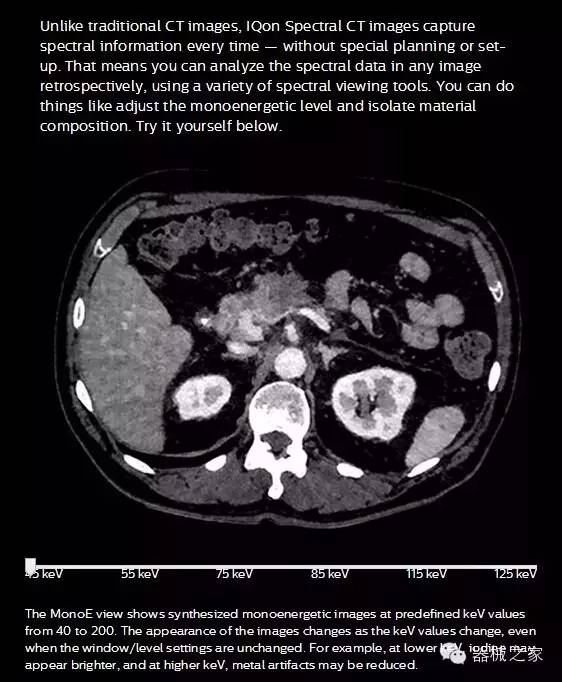

IQon光譜CT能夠按照需求提供光譜量化和工具,并能通過簡單工作流程、在低劑量下對結構進行定性分析

IQon光譜CT -- 是業(yè)界首臺以探測器為成像基礎的光譜CT,它可以在單次常規(guī)掃描下獲得傳統解剖影像及光譜功能影像。不僅可以提供精準的診斷信息,還可簡化工作流程、在低劑量下完成定量與定性分析。